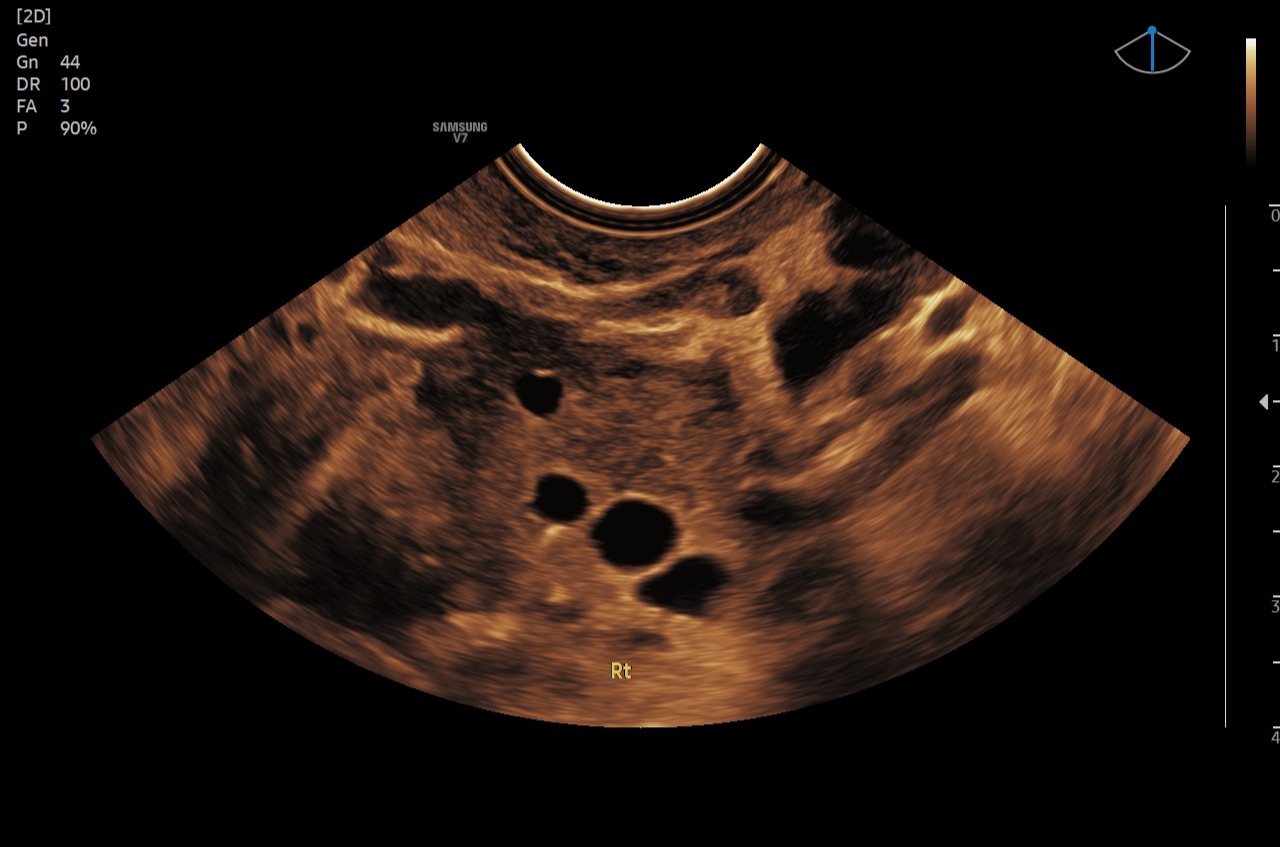

Fertiliteitsecho's

Een fertiliteitsecho is een inwendige echo die wordt uitgevoerd om inzicht te krijgen in je vruchtbaarheid. Deze echo kan bijvoorbeeld worden ingezet bij een kinderwens, het volgen van je cyclus of een fertiliteitstraject.

Eén van onze echoscopisten is gespecialiseerd in het uitvoeren van deze fertiliteitsecho’s. Tijdens de echo wordt gericht gekeken naar onder andere de baarmoeder, de eierstokken en het aantal eiblaasjes (follikels). De resultaten ontvang je direct na afloop digitaal, zodat je deze kunt delen met je behandelend arts of fertiliteitskliniek.